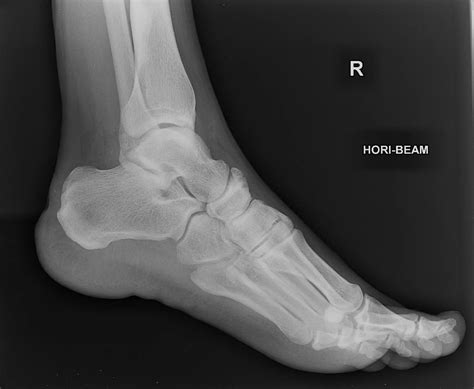

A Calcaneus X Ray is a medical imaging technique used to visualize the calcaneus, or heel bone. This type of X-ray is particularly useful for diagnosing fractures, dislocations, and other abnormalities in the heel area. The calcaneus is the largest bone in the foot and is subject to significant stress and impact, making it prone to injuries, especially in athletes and individuals involved in high-impact activities.

Interpreting the results of a Calcaneus X Ray requires the expertise of a radiologist or orthopedic specialist. The images are carefully examined for signs of fractures, dislocations, or other abnormalities. Here are some common findings that may be identified:

• Fractures: These can range from simple cracks to complex fractures involving multiple bone fragments. The location and severity of the fracture will determine the appropriate treatment.

• Dislocations: These occur when the bones in the heel area are displaced from their normal position. Dislocations can cause significant pain and may require surgical intervention.

• Bone Spurs: These are bony projections that can form on the heel bone due to chronic stress or inflammation. Bone spurs can cause pain and discomfort, especially during weight-bearing activities.

• Arthritis: X-rays can also reveal signs of arthritis, such as joint space narrowing and bone spurs, which can affect the heel and surrounding joints.